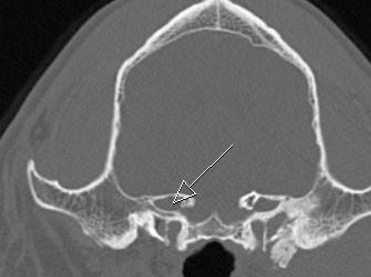

orbital fissure